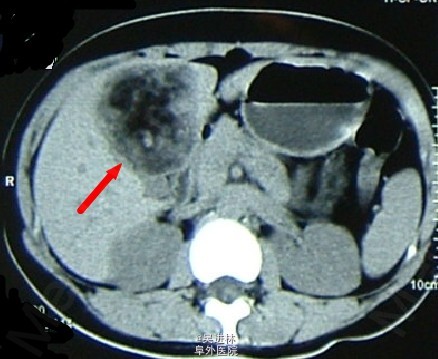

肝血管平滑肌脂肪瘤是一种含脂肪组织的肝脏良性肿瘤,包括平滑肌、血管及成熟型脂肪细胞三种组织学成分。临床无明显症状。据搜狗百科介绍,到目前为止世界文献共报道29例!!本例患者男,45岁,为体检发现肝区占位就诊。